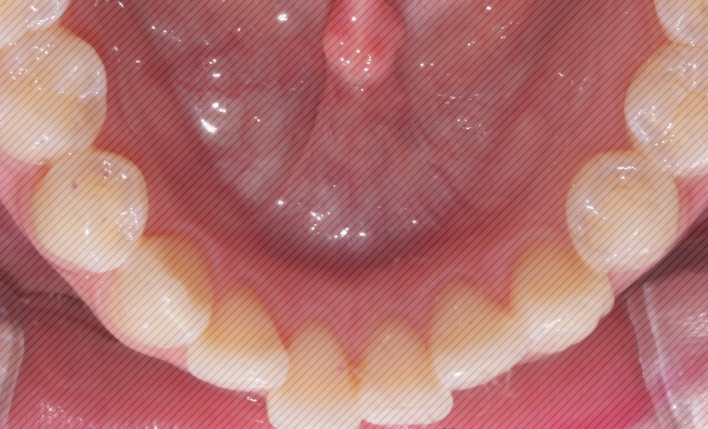

2D교정 교정기간 : 4개월

상악 오른쪽 앞니의 부분 돌출도

이상없이 고르게 교정이

완료 되었습니다.

하악 크라우딩

(자리가 없어 덧난 경우) 도

예쁘게 제자리를 찾아 갔습니다.

4개월만에 개선된 모습을 보니

환자분도 굉장히 만족해하셨는데요.